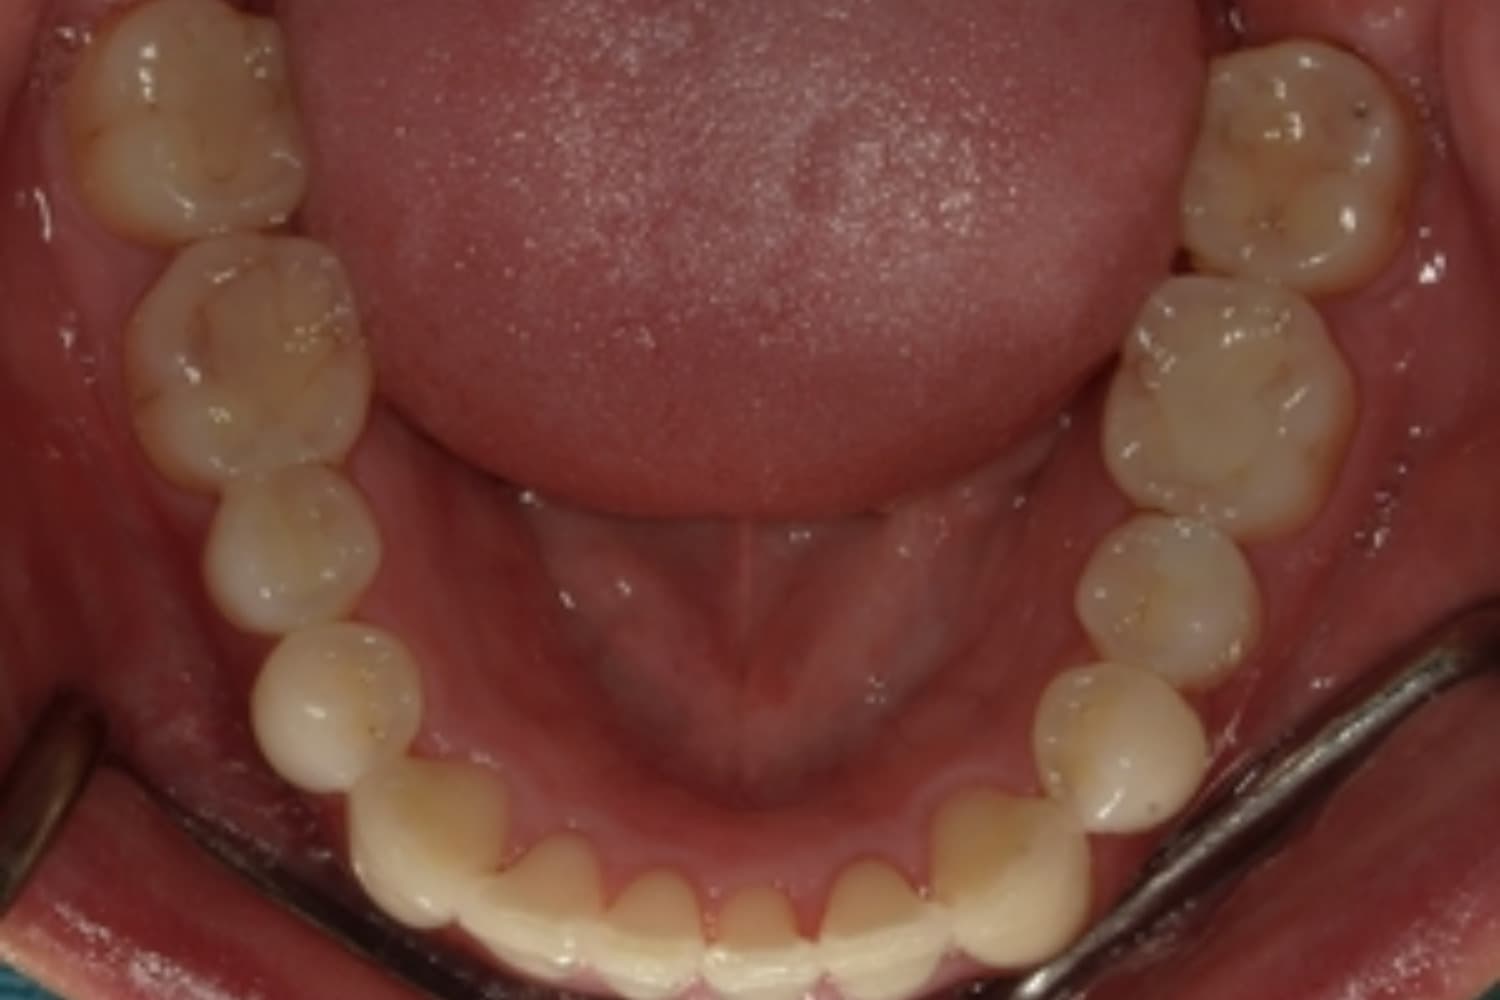

ガタガタとした歯並びや八重歯(1)

Before

After

ガタガタとした歯並びや八重歯をマウスピース矯正(インビザライン)にて治療

主訴

下の前歯のガタガタが気になる

治療期間

2年5カ月

費用

90万円

副作用・リスク

・矯正治療による歯の動きには個人差があり、想定より治療期間が延びることがあります。 ・矯正治療で歯を動かす際に痛みをともなうことがあります。 ・指示された通りに保定装置を装着しないと、歯並びや噛み合わせの後戻りを引き起こす可能性があります。